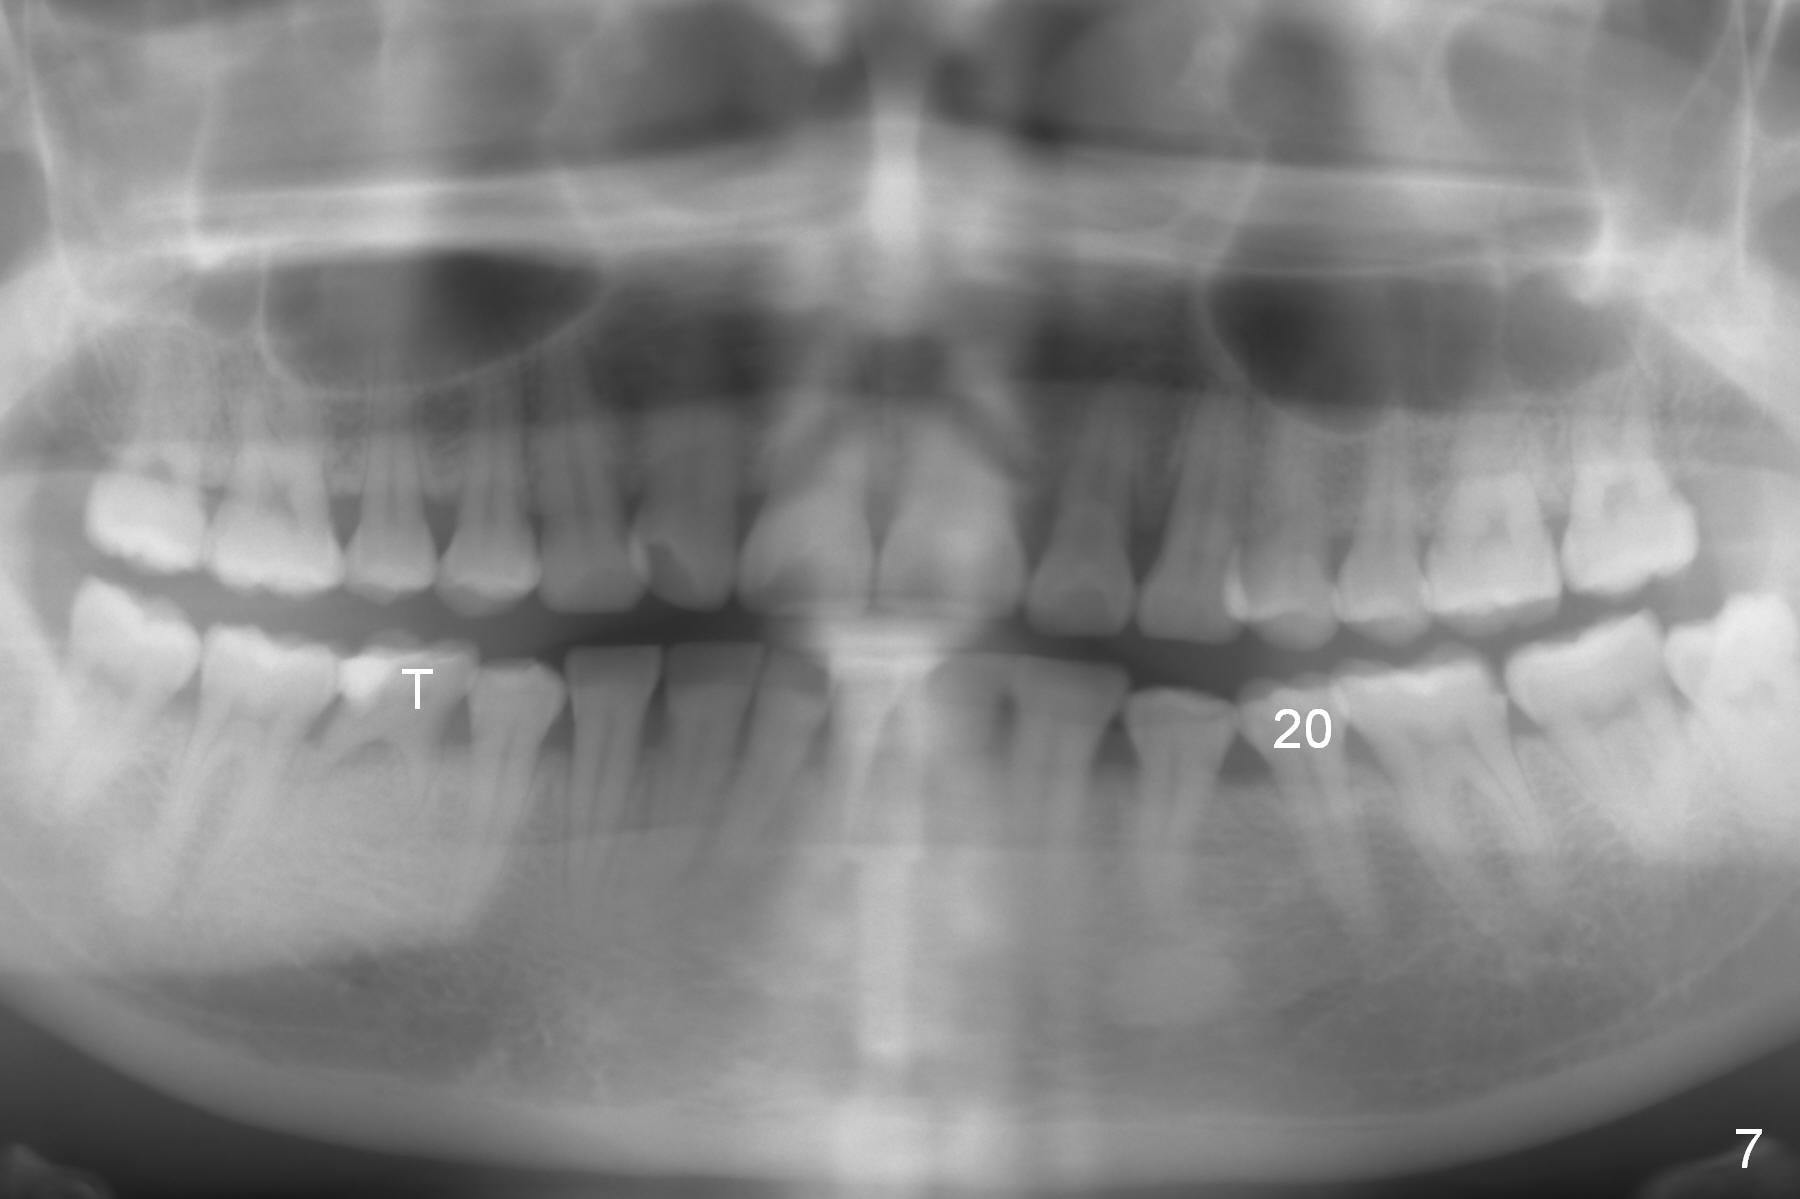

Panoramic X-ray shows underdevelopment of #20 and 29 tooth buds (Fig.6), which is related to K and T being retained (Fig.3). What should be done for K and T as well as 20 and 29?

The patient's mother is 38 years old. She reports that her tooth #20 took long time to erupt. The tooth T remains retained (Fig.7). The patient's 5-year-old sister appears to be normal in tooth bud development (Fig.8).